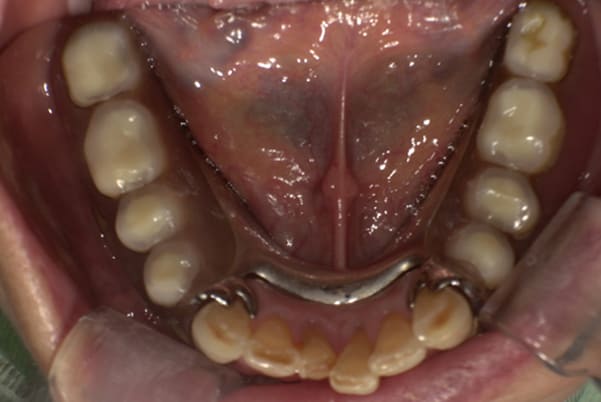

下顎治療前

-

下顎治療後

治療前の入れ歯の奥歯は、治療後の義歯と比較しても分かるように、歯が削れ平らになった状態です。

これにより奥歯のかみ合わせは低くなり、前歯のみが強くあたり、かみ合わせにより上の前歯大きな負担がかかっていたことにより、上の前歯が折れたことが考えられます。